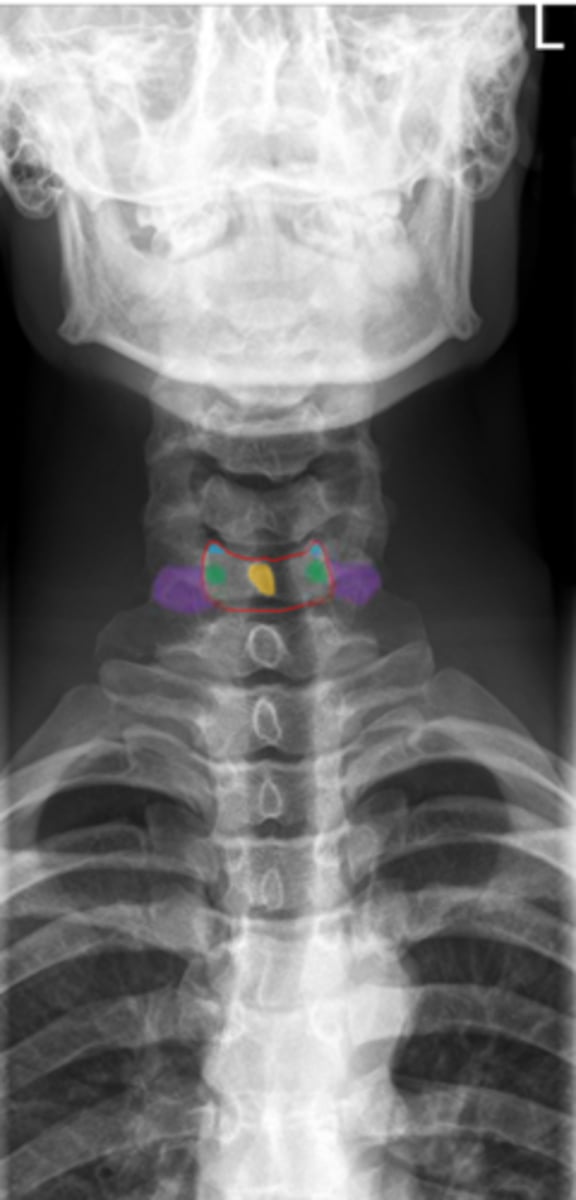

uncinate process

Identify the blue structure

transverse process

Identify the purple structure

pedicles

Identify the green structure

spinous process

Identify the yellow structure

C1 and C2

What vertebrae is being examined?

Odontoid process (dens)

Identify the purple structure

anterior arch/tubercle

Identify the red structure

posterior arch/tubercle

Identify the green structure

lateral masses

Identify the blue structure